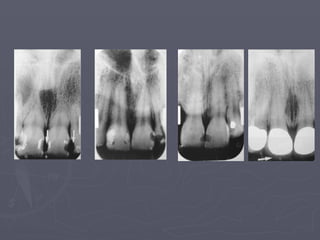

Maxilla

Radiolucent Landmarks

1- Intermaxillary

suture

2- Nasal Fossa

3- Incisive foramen

4- Lateral Fossa

5- Superior foramina

of the nasopalatine

canals

Radiopaque Landmarks

1- Anterior nasal spine

2- Shadow of the nose

3- Zygomatic process

and zygomatic bone

4- Nasolabial fold

5- Pterygoid plates

Intermaxillary Suture

►Appears on intraoral radiographs as a thin

radiolucent line in the midline between the

two portions of the premaxilla.

►Bordered by two radiopaque borders.

►Its appearance depends on both anatomic

variability and x-ray angulation.

►Misinterpreted as fracture.

Nasal Fossa

►It appears in the central incisors projection.

►Nasal septum may appear.

►The shadow of the inferior chonchae may

appear extending laterally toward the nasal

septum.

►Misinterpreted as periapical pathosis

Incisive Foramen

► Also called anterior palatine or nasopalatine

foramen.

► It lies in the midline of the maxilla behind the

central incisors.

Lateral Fossa

► Also called incisive fossa, is a

gentle depression in the

maxilla near the lateral

incisor.

► On periapical projection of

this region, it may appear

diffusely radiolucent.

► Misinterpreted as pathosis.